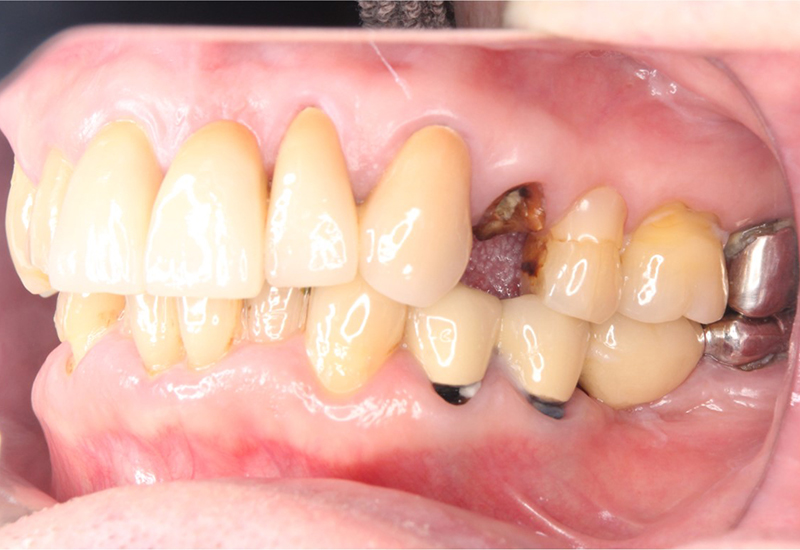

治療前 |